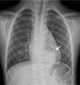

Foregut cyst